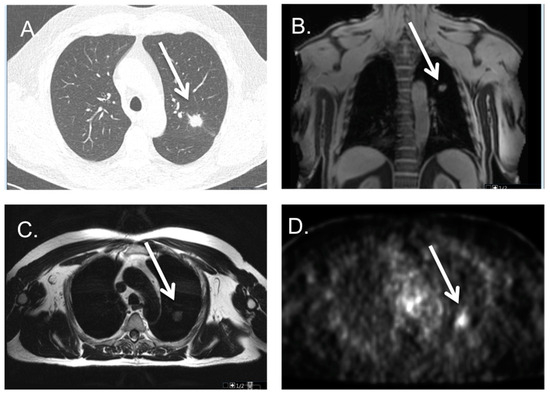

3.4. Lung Metastases